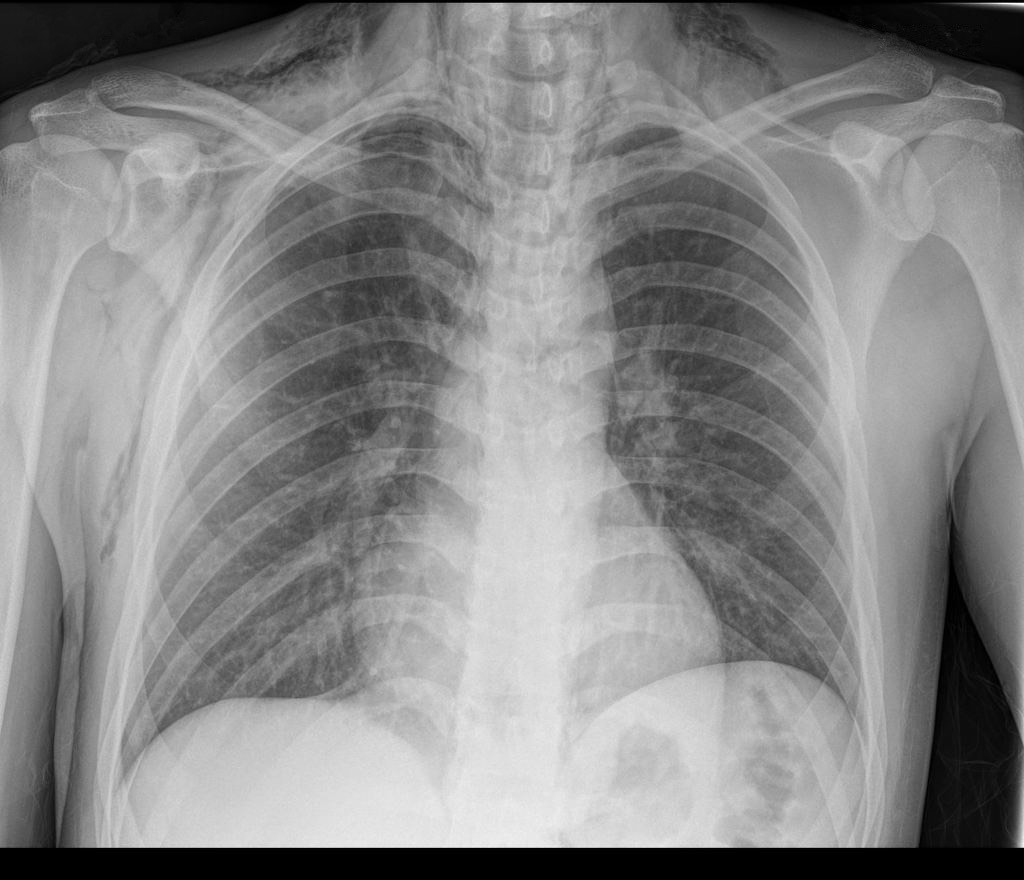

2859. Рентгенологические данные, представленные на снимкегрудной клетки кардиологического пациента,

который обратился с жалобами на одышку и нелокализованную боль в левой половине грудной клетки после интенсивного приступа рвоты на фоне алкогольного опьянения, наиболее вероятно, соответствуют клинической картине